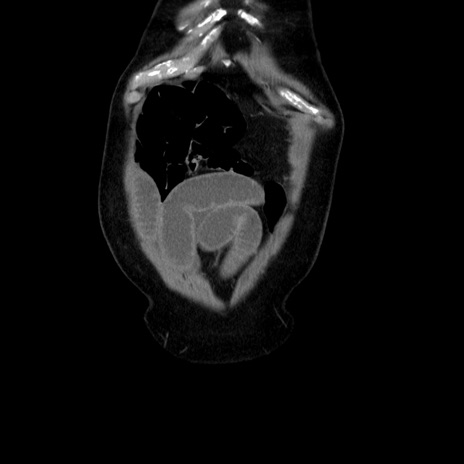

横断像

【症例】80歳代男性

【主訴】臍周囲痛

【現病歴】約6時間前から臍下部痛が出現。次第に腹部膨隆・背部痛も生じてきたため来院。背部痛の場所は変化しない。

【身体所見】意識清明、BT 36.3℃、BP  131/87mmHg、P 87bpm、SpO2 100%(RA)、臍周囲自発痛・圧痛あり、反跳痛なし、自発痛部位に一致して板状硬あり、腹部膨隆、腸雑音減弱、CVA tenderness両側陰性。

【データ】WBC 19600、CRP 0.33